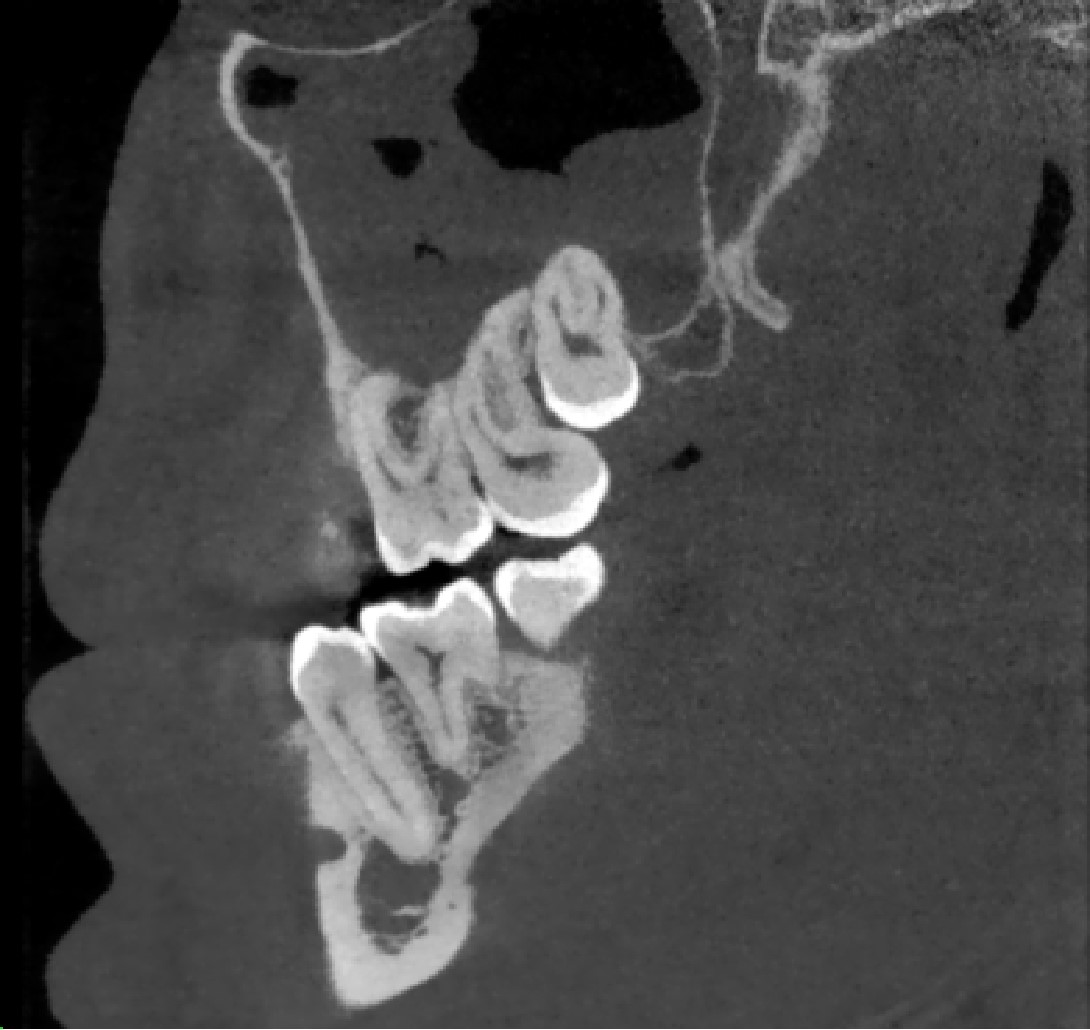

Інформація про форму коренів зуба, ширину та висоту кістки, розташування гайморових пазух та нижньощелепного нерву, для уникнення ризиків і ускладнень під час видалення та імплантації зубів.

Визначення складної канально-кореневої системи, наявність періапікальних змін, пошук додаткових каналів зуба, які можна пропустити при ендодонтичному лікуванні.